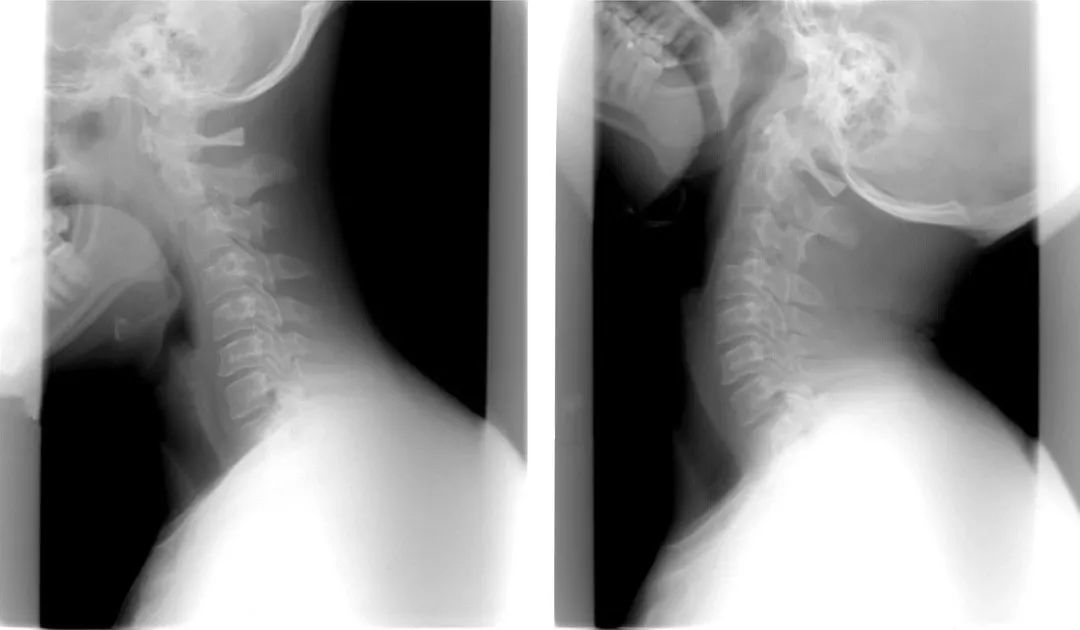

樂活有方【 健康專欄 - 頸椎不適可能影響身體六大問題!】

頸椎不適可能影響身體六大問題!

可見頸椎出問題,不僅僅只是脖子疼這麼簡單,它的危害可能出乎你的意料!

頸椎不適別忽略,小心引發大問題!

頸椎的位置太關鍵,而它的病變過程往往又能持續數年,很難被察覺。等出現相應症狀時,還可能伴隨比較嚴重的並發症。